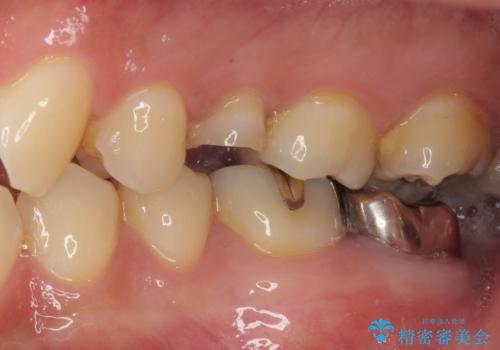

インプラント処置は、抜歯即時埋入を行い、十分な安定性が確認できたため、当日仮歯を装着しました。

インプラントが生着するのを待っている間に反対側の根管治療を行い、左右同時に補綴治療を行いました。

補綴治療後3ヶ月での経過は良好で、引き続き経過観察を行っていきます。